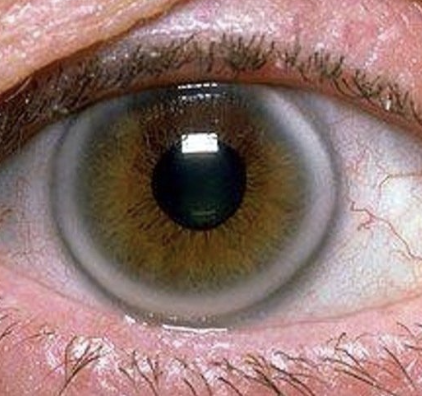

Areus senilis

Normal Findings for 10. Inspect the cornea and lens

Areus Senilis

One of the Normal Findings for 10. Inspect the cornea and lens

Normal condition in older clients

White arc around the limbus

Has no effect on vision